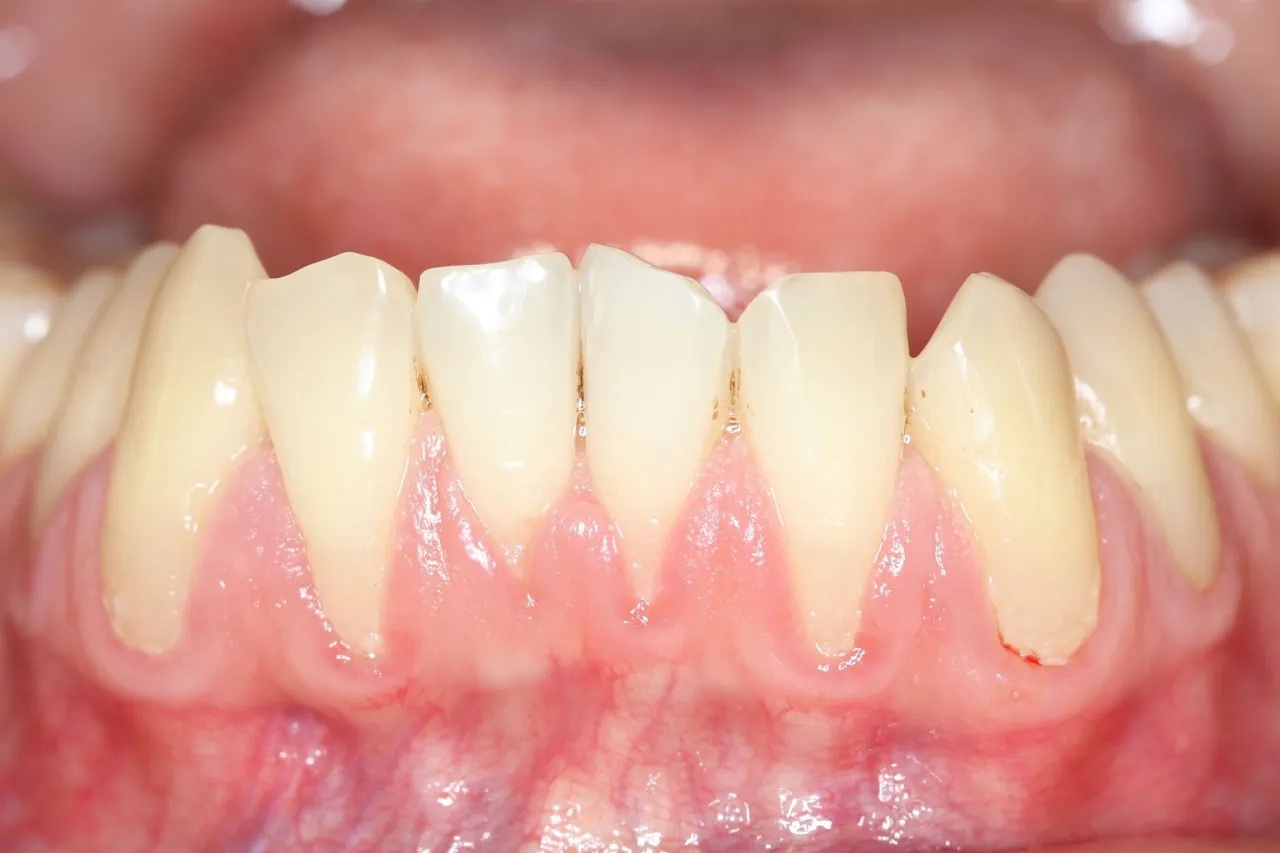

- Główne objawy to wizualne wydłużenie zębów, nadwrażliwość na zimno/ciepło oraz widoczne odsłonięcie żółtawego korzenia.

- Wizualne wydłużenie się zębów: To jeden z najbardziej oczywistych objawów. Zęby wydają się dłuższe, ponieważ więcej ich powierzchni jest widoczne.

- Widoczne odsłonięcie żółtawego korzenia: Korzeń zęba ma naturalnie ciemniejszy, żółtawy odcień niż korona, więc jego odsłonięcie jest łatwo zauważalne.

Recesja dziąseł to proces, który rzadko pojawia się nagle. Zazwyczaj zaczyna się od subtelnych zmian niewielkiego cofnięcia brzegu dziąsła, które może być niezauważone przez pacjenta. Z czasem jednak, pod wpływem utrzymujących się czynników przyczynowych, recesja pogłębia się, odsłaniając coraz większą część korzenia. Początkowa nadwrażliwość może przerodzić się w stały dyskomfort, a estetyczny problem w poważne zagrożenie dla stabilności i zdrowia zęba. To dlatego tak ważne jest, aby nie bagatelizować nawet najmniejszych sygnałów i podjąć interwencję na wczesnym etapie, zanim recesja stanie się trudna do opanowania.